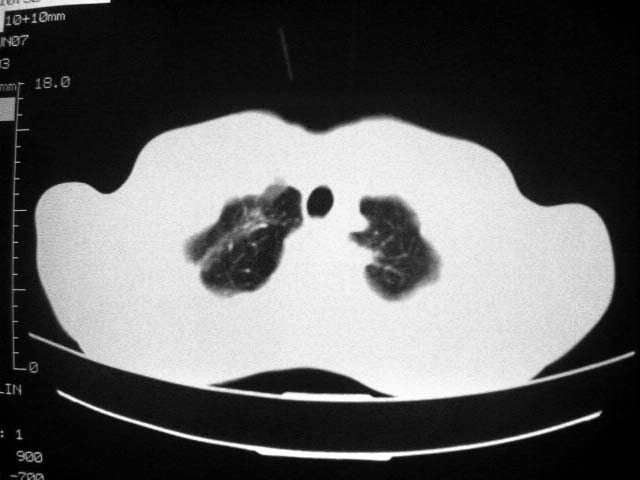

标题: CT7988D:近期图像 出乎意料!

从ct7988c 至今未用任何抗生素及抗痨药,维持保肝治疗。患者低热、咳血渐消失。

07年6月22号复查

前几次大家认为是转移癌,但此次复查病灶却明显吸收好转,不支持诊断。请大家讨论。[emb10]